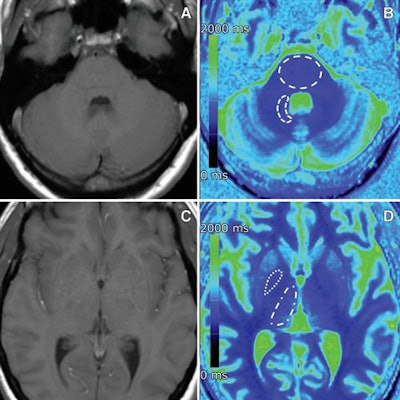

However, there were significantly shorter T1 relaxation times in the globus pallidus among patients with normal renal function and multiple administrations of gadobutrol, compared with control subjects with normal renal function. The difference between the two groups was 226.2 msec (p = 0.002).

MR images of a 40-year-old woman with osteosarcoma who received 20 single doses of gadobutrol between 2007 and 2017. Transverse native T1-weighted spin-echo MR images (A, C) and corresponding transverse color-coded multiplanar reconstructions (B, D) of T1 maps. Images courtesy of Radiology.While more research is needed to draw a definitive conclusion between T1 relaxation times and gadolinium deposition, the results "support the concept that patients should be informed about the possibility of subclinical gadobutrol brain retention before undergoing contrast agent-enhanced MRI," the authors wrote.